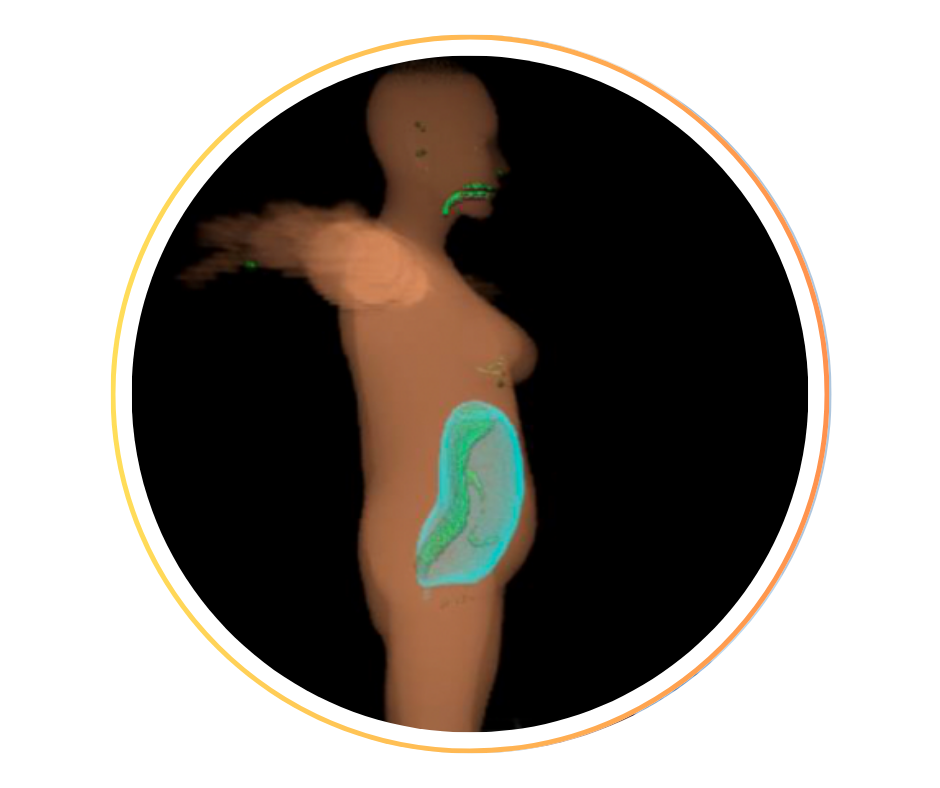

• Chirurgie fœtale in utero, de l’imagerie aux traitements :

modélisation de scènes chirurgicales pour une visualisation en VR, volumétries fœtales et d’organes.